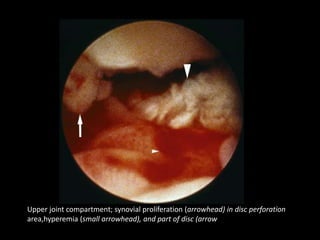

Upper joint compartment; synovial proliferation (arrowhead) in disc perforation

area,hyperemia (small arrowhead), and part of disc (arrow

Same joint; synovial proliferation (arrowhead) in disc perforation area,

and part of disc (arrow)

Upper joint compartment;synovial proliferation (arrowhead) in disc perforation area,hyperemia (small arrowhead), and part of disc (arrow

• 127.

Same joint; synovialproliferation (arrowhead) in disc perforation area, and part of disc (arrow)